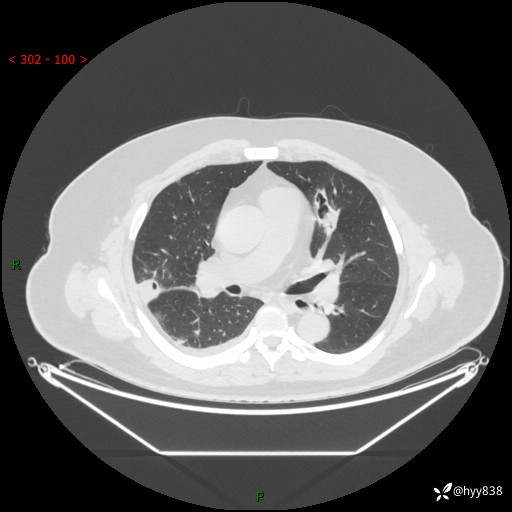

病例信息

性别:男

年龄:48岁

简要病史:发热来诊(门诊病人)

胸部CT平扫